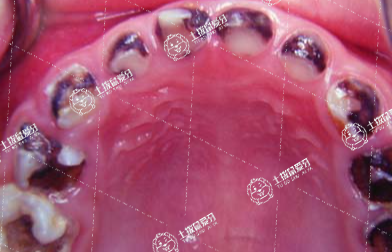

隨著社會(huì)的進(jìn)一步發(fā)展,越來越多的牙友們總是在日常生活中開始重視牙齒健康,不過,總會(huì)容易出現(xiàn)差池,不少牙友們?nèi)菀壮霈F(xiàn)齲齒的現(xiàn)象,當(dāng)齲齒出現(xiàn)后需要牙友們及時(shí)去拔牙修復(fù),拔牙后多久可以鑲牙最合適的?這或許是牙友們比較在意的事情,接下來,我們一起來了解一下。

拔牙后三個(gè)月再鑲牙最好。

1.牙齒拔除后,牙槽窩需要愈合改建,最初的一個(gè)月牙槽骨的改變是最大的,然后逐漸穩(wěn)定,三個(gè)月完成,此時(shí)可以進(jìn)行修復(fù)治療。

2.如果提前修復(fù)治療,口腔頜骨吸收還沒有穩(wěn)定,做出來的義齒會(huì)和三個(gè)月后的頜骨之間存在縫隙,導(dǎo)致不密合、食物嵌塞等癥狀。

3.當(dāng)然,也不是越晚最好,拔除后牙齒如果不及時(shí)修復(fù),對(duì)頜的牙齒會(huì)伸長(zhǎng),臨近牙齒會(huì)向缺隙側(cè)傾斜,導(dǎo)致修復(fù)空間缺失;此外由于頜骨缺乏刺激,骨質(zhì)會(huì)出現(xiàn)疏松,為防止這種現(xiàn)象,可以制作間隙保持器、臨時(shí)牙等。